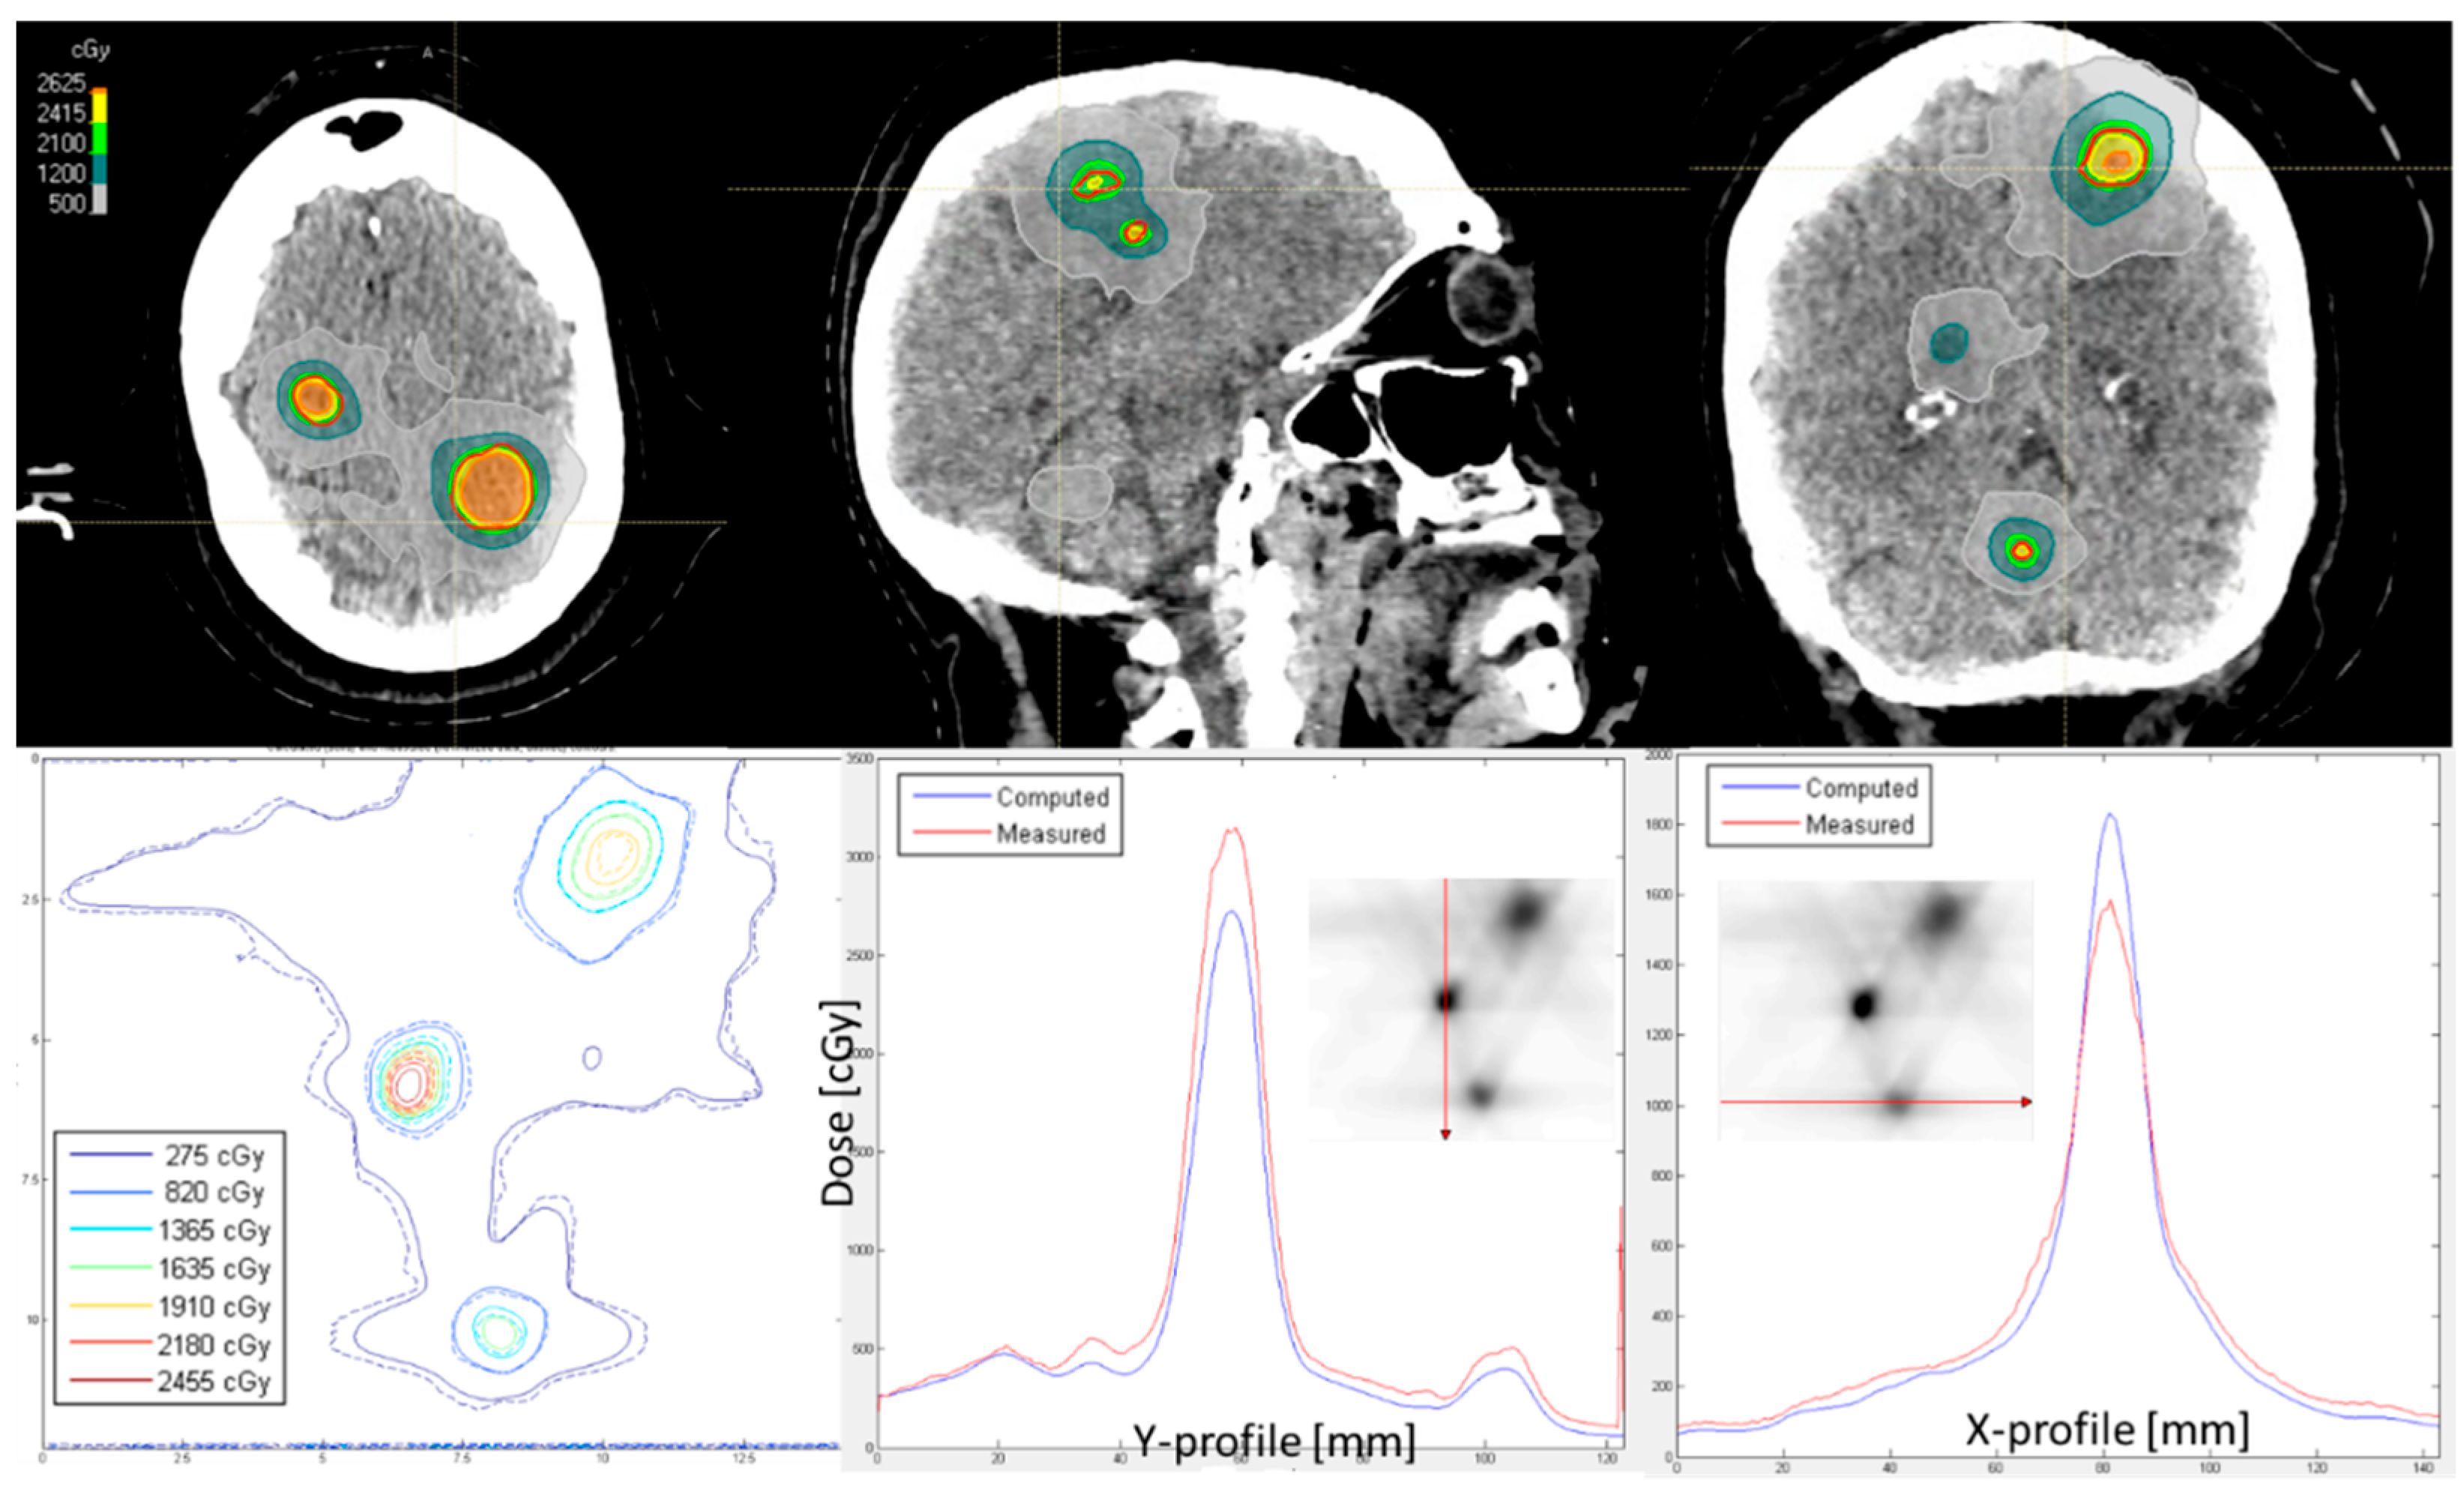

2.3. Film Dosimetry and Secondary Dose Calculation

- If the passing rate for the global dose difference of 3% and 1 mm distance-to-agreement was >95%, the plan could be approved by a medical physicist.

- If the passing rate for a global dose difference of 3% and 1 mm distance-to-agreement was 85–95%, and the dose differences were in the low dose range, then the plan could also be approved. If they were in the high dose range, then we checked whether the dose differences were small (within 5%) or large (5–10%) by calculating a relative percent difference to the global dose. We investigated whether it was possible to find out where this difference came from. It could be verified whether doses of the high dose of 15 Gy and the low dose of 0 Gy were measured. We performed the film dosimetry on a different matched LINAC to confirm the results. If necessary, and in consultation with a radiation oncologist, the plan was adjusted.

- If the passing rate for a global dose difference of 3% and 1 mm distance-to-agreement was <85%, we investigated whether it was possible to find out where this difference came from (for example, wrong unexposed film or dose calibration used, wrong orientation during scanning). If necessary, and in consultation with a radiation oncologist, the plan was adjusted.